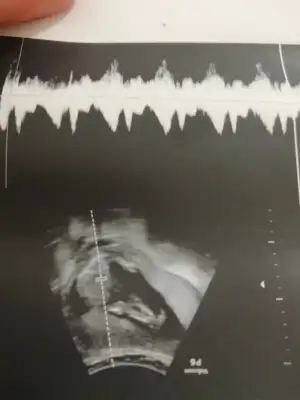

Merhaba tahminde bulunurmusunMaalesef üreme organını göremedim

CİNSİYET TAHMİNİİİİİ

Kimler kimler yazdı?Ueni fotoğrafı var bu gün gittik hiç hareket etmedi böbrek için ultrasona gittik o doktor erkek5. Bebek benim görüşüm dediNubunu kapatmis kafa yapisi yuvarlak kiz olbilir genelde koseli olunca erkek oluyo

Bence erkek bariz belli.Eki Görüntüle 3178479 bize de erkek dedi 16, haftadayız sizce yanılma payı olabilir mi ikinci fotoğraftaki organı mı acaba

Ueni fotoğrafı var bu gün gittik hiç hareket etmedi böbrek için ultrasona gittik o doktor erkek5. Bebek benim görüşüm dedi

Benim 7 haftalık bakabilirmisiniz acaba rica etsenÇok tutarlı diyemem ama ben hamileyken arkadaşlarla hep dikkat etmiştik kız bebeğin başı sağda erkek bebeğin başı solda oluyodu ultrason fotosunda varsayım yani7-8 haftalık fotosu varsa daha net söyleyebilirim ama

Gülüm erkek diyebilirim hayirli olsun7 haftalık

Çok tutarlı diyemem ama ben hamileyken arkadaşlarla hep dikkat etmiştik kız bebeğin başı sağda erkek bebeğin başı solda oluyodu ultrason fotosunda varsayım yani7-8 haftalık fotosu varsa daha net söyleyebilirim ama